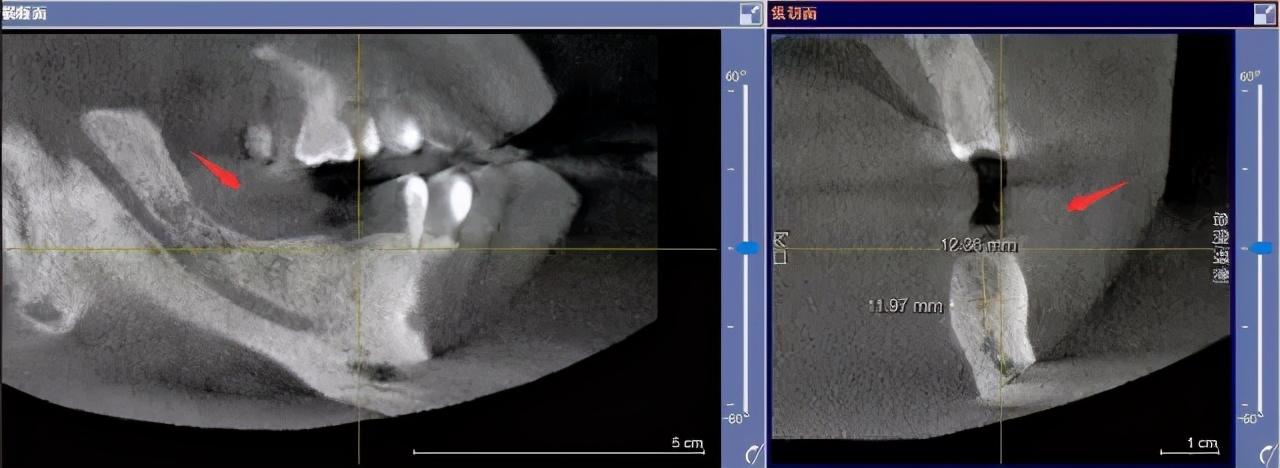

step1

先要做一個口腔全景片、頜骨CT等

醫(yī)生根據(jù)機(jī)器成像查看口腔的具體情況,

是否有炎癥、牙槽骨的密度、吸收狀況

以及鄰牙組織、牙體組織等。

注明:此數(shù)據(jù)僅作模擬,不是確切種植數(shù)據(jù)。

如果僅靠雙眼大致估測口內(nèi)數(shù)據(jù),是無法得到的高度、寬度的,也無法確認(rèn)骨頭吸收多少,是否需要植入骨粉。

對后期手術(shù)有一定的影響。

通過全景片可以“解剖”牙齒測量,適宜的種植角度也可確定,健康有保障。